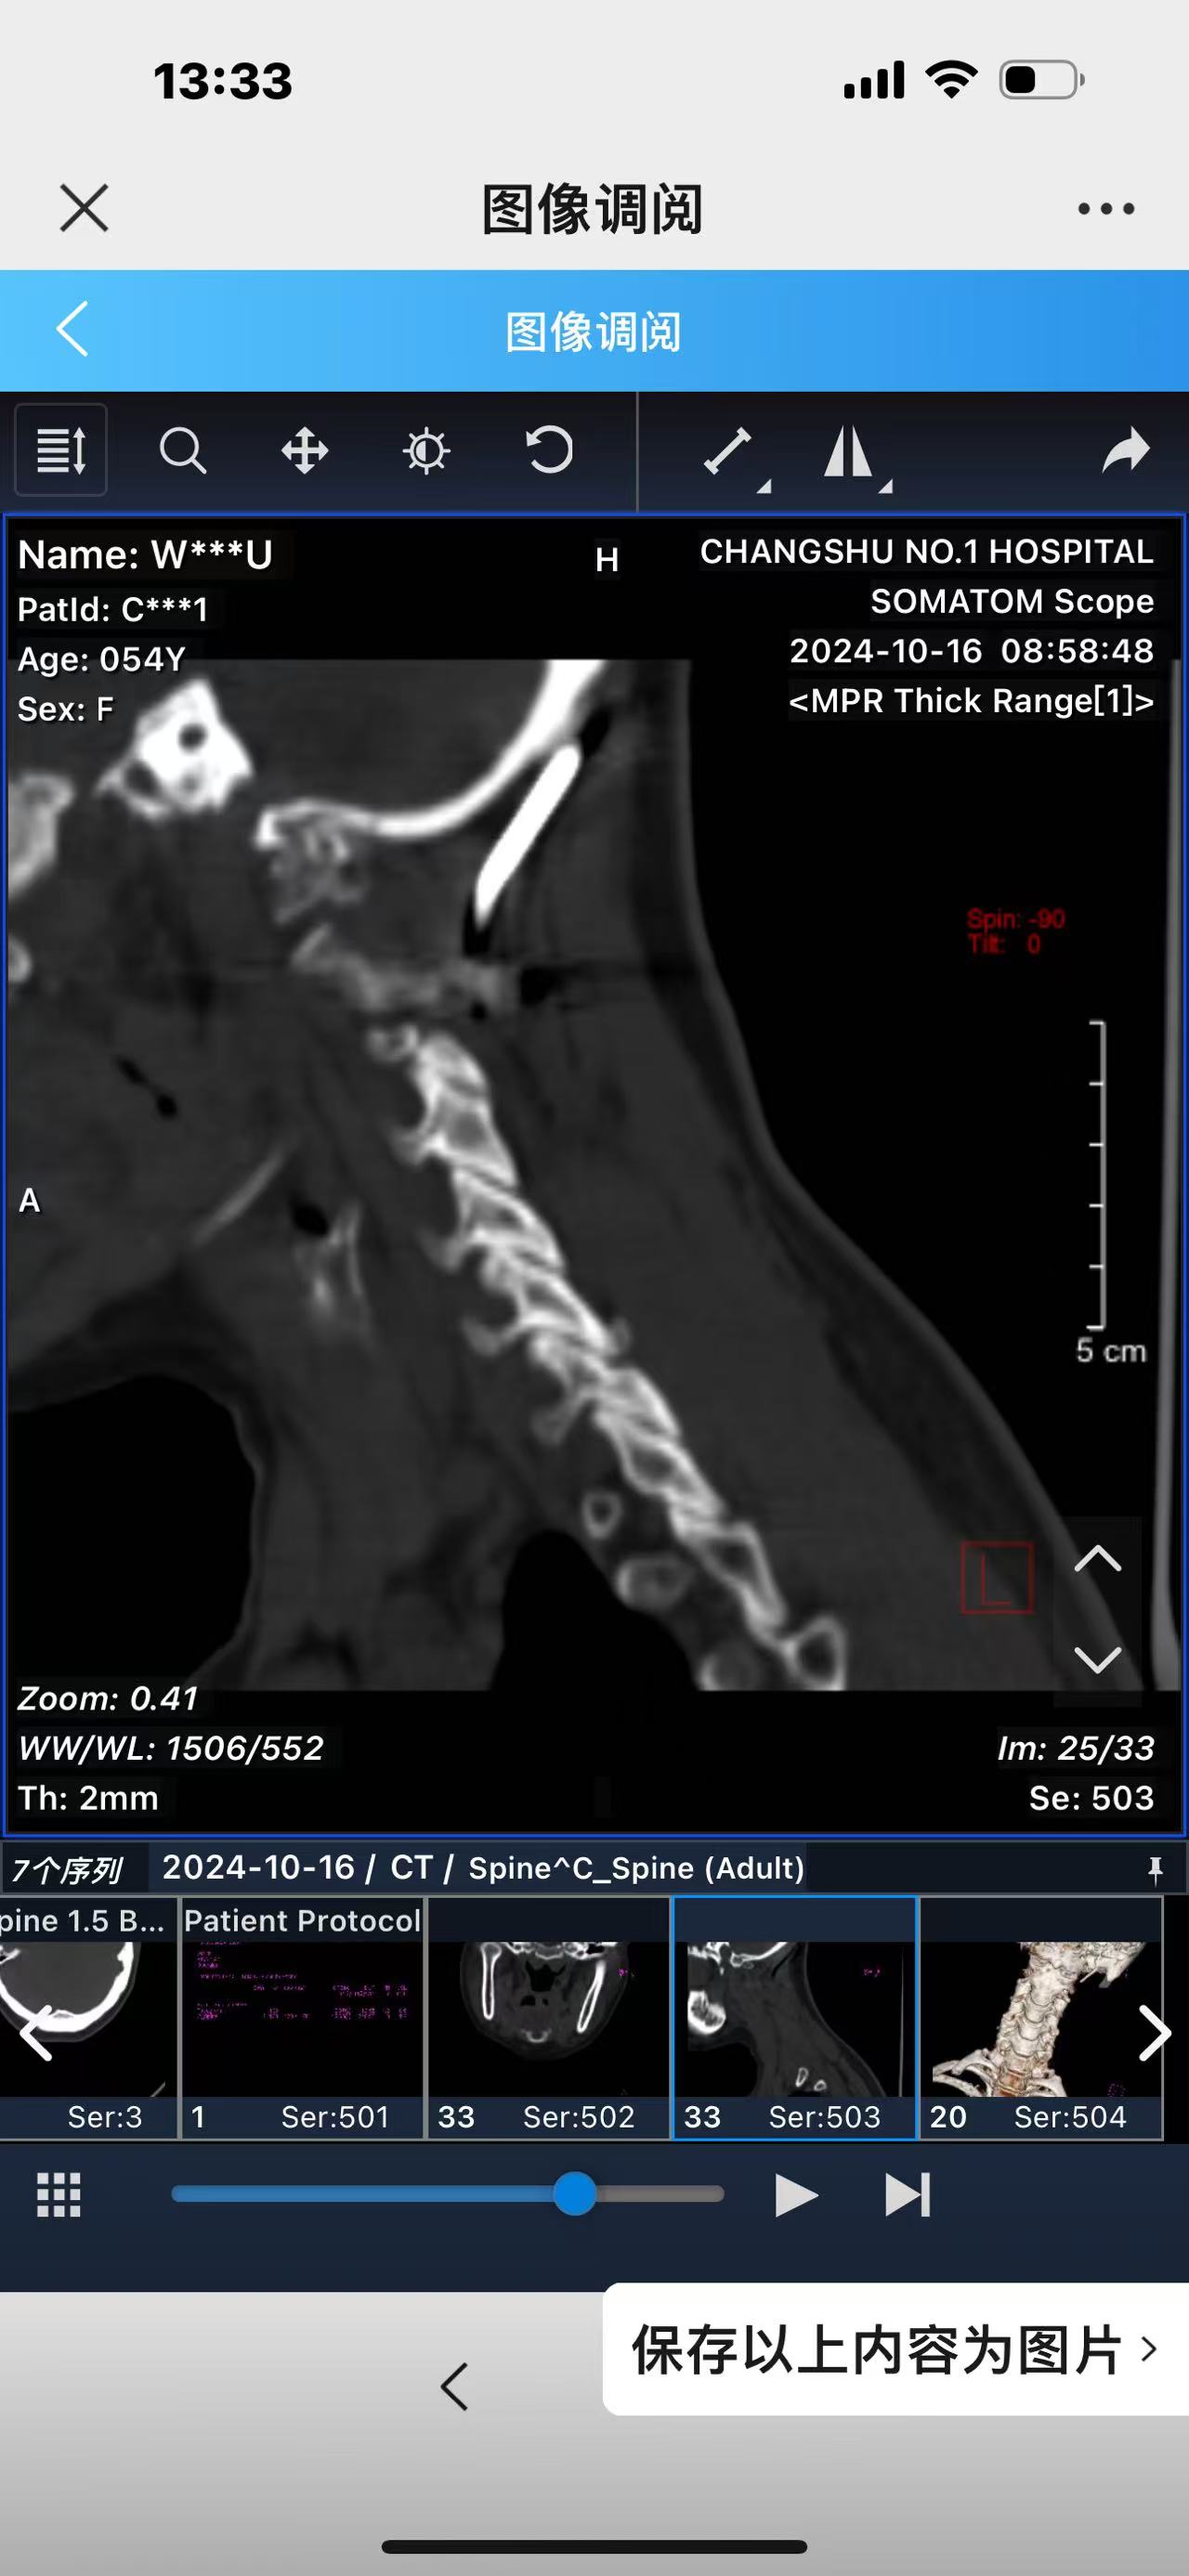

• 术后影像: